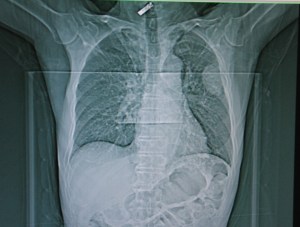

Over the continuing course of his treatment, a large opening on the anterior chest was created surgically.  Due to the extent of necrotic tissue, this required the removal of anterior sections of ribs #2, 3, 4 and 5, leaving the patient with a very large open cavity, as seen in CT slices (pulmonary and tissue windows).

BPF CT1

packing material can be seen in the right chest cavity.

tissue window showing extent of wound

This large cavity was left open for a period of around two years, while infected material was debrided and evacuated, and aggressive wound management was continued.  At the time of his presentation to the operating room, the wound bed is dry and pink with a small amount of slough.  An opening to the bronchus is visible (with bubbling on respiration at the site of the wound). The wound measures approximately  6 cm X 4 cm.  As seen from the CT images above, the wound was also several centimeters in depth.